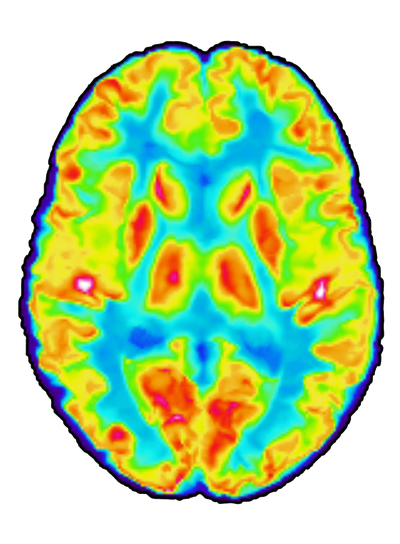

We aim to develop biomarkers and new treatments for neurodegenerative diseases. We do this by applying medical imaging techniques, such as MRI, PET and CT, to pre-clinical models of neurodegeneration, as well as human patients. Currently, we are running an academically sponsored phase IIa trial in early Alzheimer’s disease, where we assess the effect of the drug sirolimus (a.k.a. rapamycin) on neurodegeneration, brain metabolism and aging processes.

Our work also involves developing and validating biomarkers of aging that can be used as endpoints in clinical trials of geroprotective compounds. To this end, we apply machine learning models to large batches of multi-modal imaging data to estimate the biological age of different organ-systems in the human body.